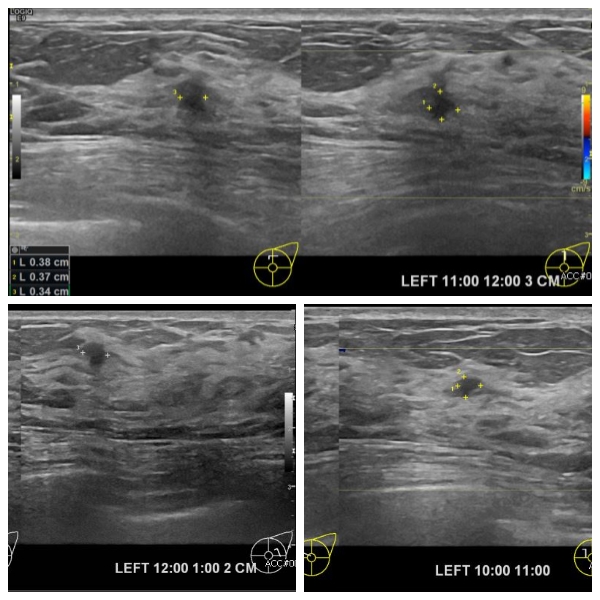

상기환자 양측유방의 멍울로 내원하신 40대 여성분으로 본원초음파상 좌측 10시 , 11시, 12시 방향에 의심스러운 멍울 조직검사 시행하여 좌측 침윤성 유관암 진단되었습니다.